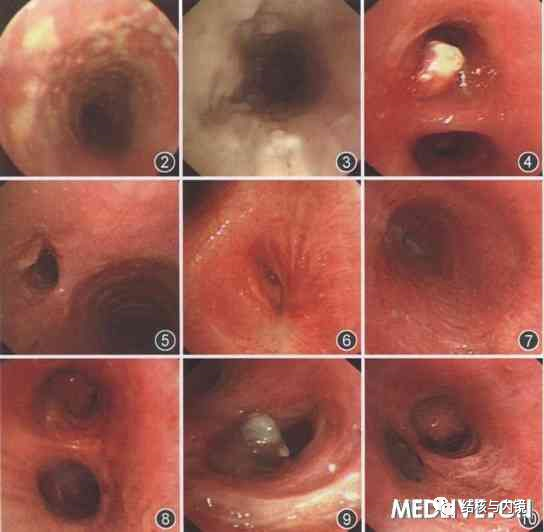

支气管镜诊断支气管结核

支气管镜检查可直视气管支气管内病灶情况;可确定支气管结核的有无;支气管结核的类型/部位/范围/严重程度;还可判断是否合并支气管狭窄以及狭窄的原因。

支气管镜介入诊断技术是支气管结核最可靠和最准确的方法

凡临床诊断肺结核,尤其是痰菌阳性,久治不愈者,合并肺不张者,不明原因长期干咳,肺部听诊有局限性哮鸣音者;临床上怀疑支气管结核的患者,尤其是伴有刺激性干咳,影像学检查无明显结核病灶而痰菌阳性的患者;原因不明的阻塞性肺炎及不明原因的呼吸困难者。在诊断时均应积极性支气管镜检查。